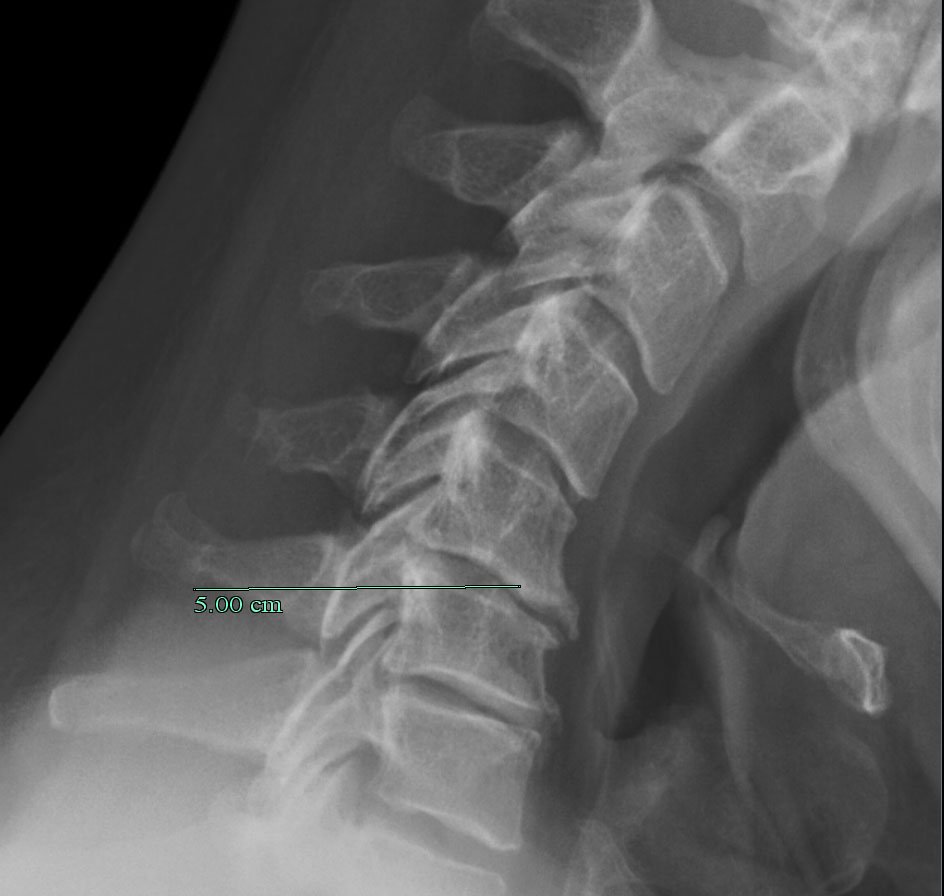

forward_large_sm

A normal X-ray of my neck, with my chin down. Note the “hooks” in the front of the affected joints - that’s spurs of bone trying to grow around the bad disc.